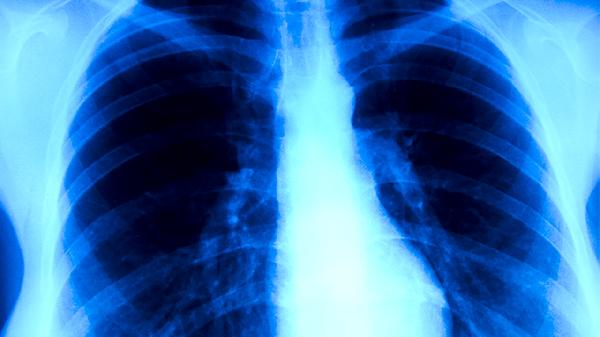

新冠感染肺部初期表現(xiàn)主要有發(fā)熱、干咳、乏力、呼吸急促、嗅覺(jué)或味覺(jué)減退等。新冠病毒感染肺部后,可能引發(fā)病毒性肺炎,早期識(shí)別癥狀有助于及時(shí)干預(yù)。

呼吸急促指安靜狀態(tài)下呼吸頻率加快,或輕微活動(dòng)后即感氣短,可能提示肺部炎癥影響氣體交換。患者應(yīng)臥床休息,采取半臥位以減輕呼吸困難。如癥狀持續(xù),需及時(shí)就醫(yī)檢查血氧飽和度,醫(yī)生可能根據(jù)情況使用糖皮質(zhì)激素如甲潑尼龍片或進(jìn)行氧療。

出現(xiàn)新冠感染肺部初期表現(xiàn)時(shí),患者應(yīng)密切監(jiān)測(cè)癥狀變化,多休息、多飲水,保持均衡飲食,攝入富含維生素C的新鮮水果蔬菜和優(yōu)質(zhì)蛋白如魚(yú)肉、豆制品。避免前往人群密集場(chǎng)所,佩戴口罩減少傳播風(fēng)險(xiǎn)。如癥狀加重如持續(xù)高熱、呼吸困難或血氧飽和度下降,須立即就醫(yī)進(jìn)行肺部CT等檢查,遵醫(yī)囑接受抗病毒或支持治療。康復(fù)期間可進(jìn)行適度呼吸功能鍛煉,如腹式呼吸,幫助肺功能恢復(fù)。